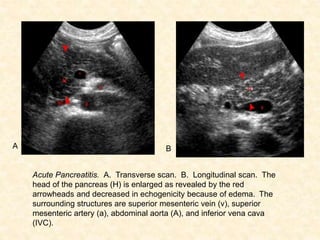

Ultrasound

• Fails to completely to completely image the

pancreas 2/2 overlying bowel gas

• Superior to CT in visualizing gallbladder and

biliary tree for gallstones

• Negative US does not rule out gallstone as

etiology because:

1. Not sensitive for common bile duct stones.

2. Only 50% of those with microlithiasis have + US.

3. View may be obstructed by ileus and underlying

structures obscured by bowel gas.

A

Acute Pancreatitis. A. Transverse scan. B. Longitudinal scan. The

head of the pancreas (H) is enlarged as revealed by the red

arrowheads and decreased in echogenicity because of edema. The

surrounding structures are superior mesenteric vein (v), superior

mesenteric artery (a), abdominal aorta (A), and inferior vena cava

(IVC).

B